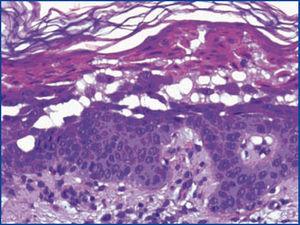

La enfermedad de Grover es una dermatosis caracterizada por exantema máculo-papular, eritematoso y pruriginoso, principalmente troncular. La enfermedad renal crónica bajo diálisis es una condición predisponente, por mecanismos no totalmente dilucidados. Comunicamos el caso de un varón de 68 años con poliquistosis renal, en diálisis peritoneal continua ambulatoria desde hace seis meses; hiperplasia prostática benigna condicionando múltiples infecciones urinarias de repetición, recibiendo tratamiento profiláctico con contrimetroprim-sulfametoxazol (TMP-SMX). Consulta por fiebre de 38 ºC, malestar general, astenia y, 48 horas antes, lesiones máculo-papulares, pruriginosas y eritematosas en el tronco y posteriormente en los miembros. A la exploración física, el paciente se halla afebril, con máculo-pápulas eritematosas en el tronco y los miembros (figura 1). La exploración física restante no presenta hallazgos relevantes. Las exploraciones complementarias evidencian bicitopenia, sin otros hallazgos contributorios. Se realiza biopsia cutánea (figura 2) que revela acantolisis suprabasal con presencia de células disqueratóticas en los estratos superficiales en forma de granos y cuerpos redondos, y leve infiltrado inflamatorio dérmico perivascular en dermis superficial, hallazgos compatibles con enfermedad de Grover. Se sustituye el uso de icodextrina por soluciones a base de dextrosa y suspensión de sulfamidas, con remisión de las lesiones cutáneas y la bicitopenia. Inicialmente planteado como posible agente etológico el TMP-SMX, se reintroduce la solución de diálisis con icodextrina, recidivando en una semana el exantema cutáneo, con mejoría con tratamiento corticoideo tópico y suspensión de la icodextrina.

Figura 2. Biopsia cutánea compatible con enfermedad de Grover